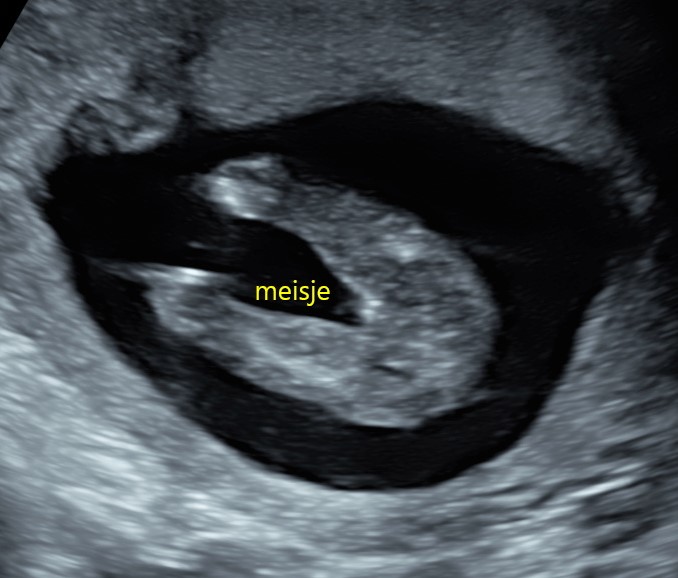

Geslachtsvoorspelling echo voorbeeld

Geslachtsvoorspelling

Wil je het geslacht weten? Vanaf ongeveer 15–16 weken kan vaak met een goede waarschijnlijkheid worden aangegeven of het een jongen of meisje wordt.